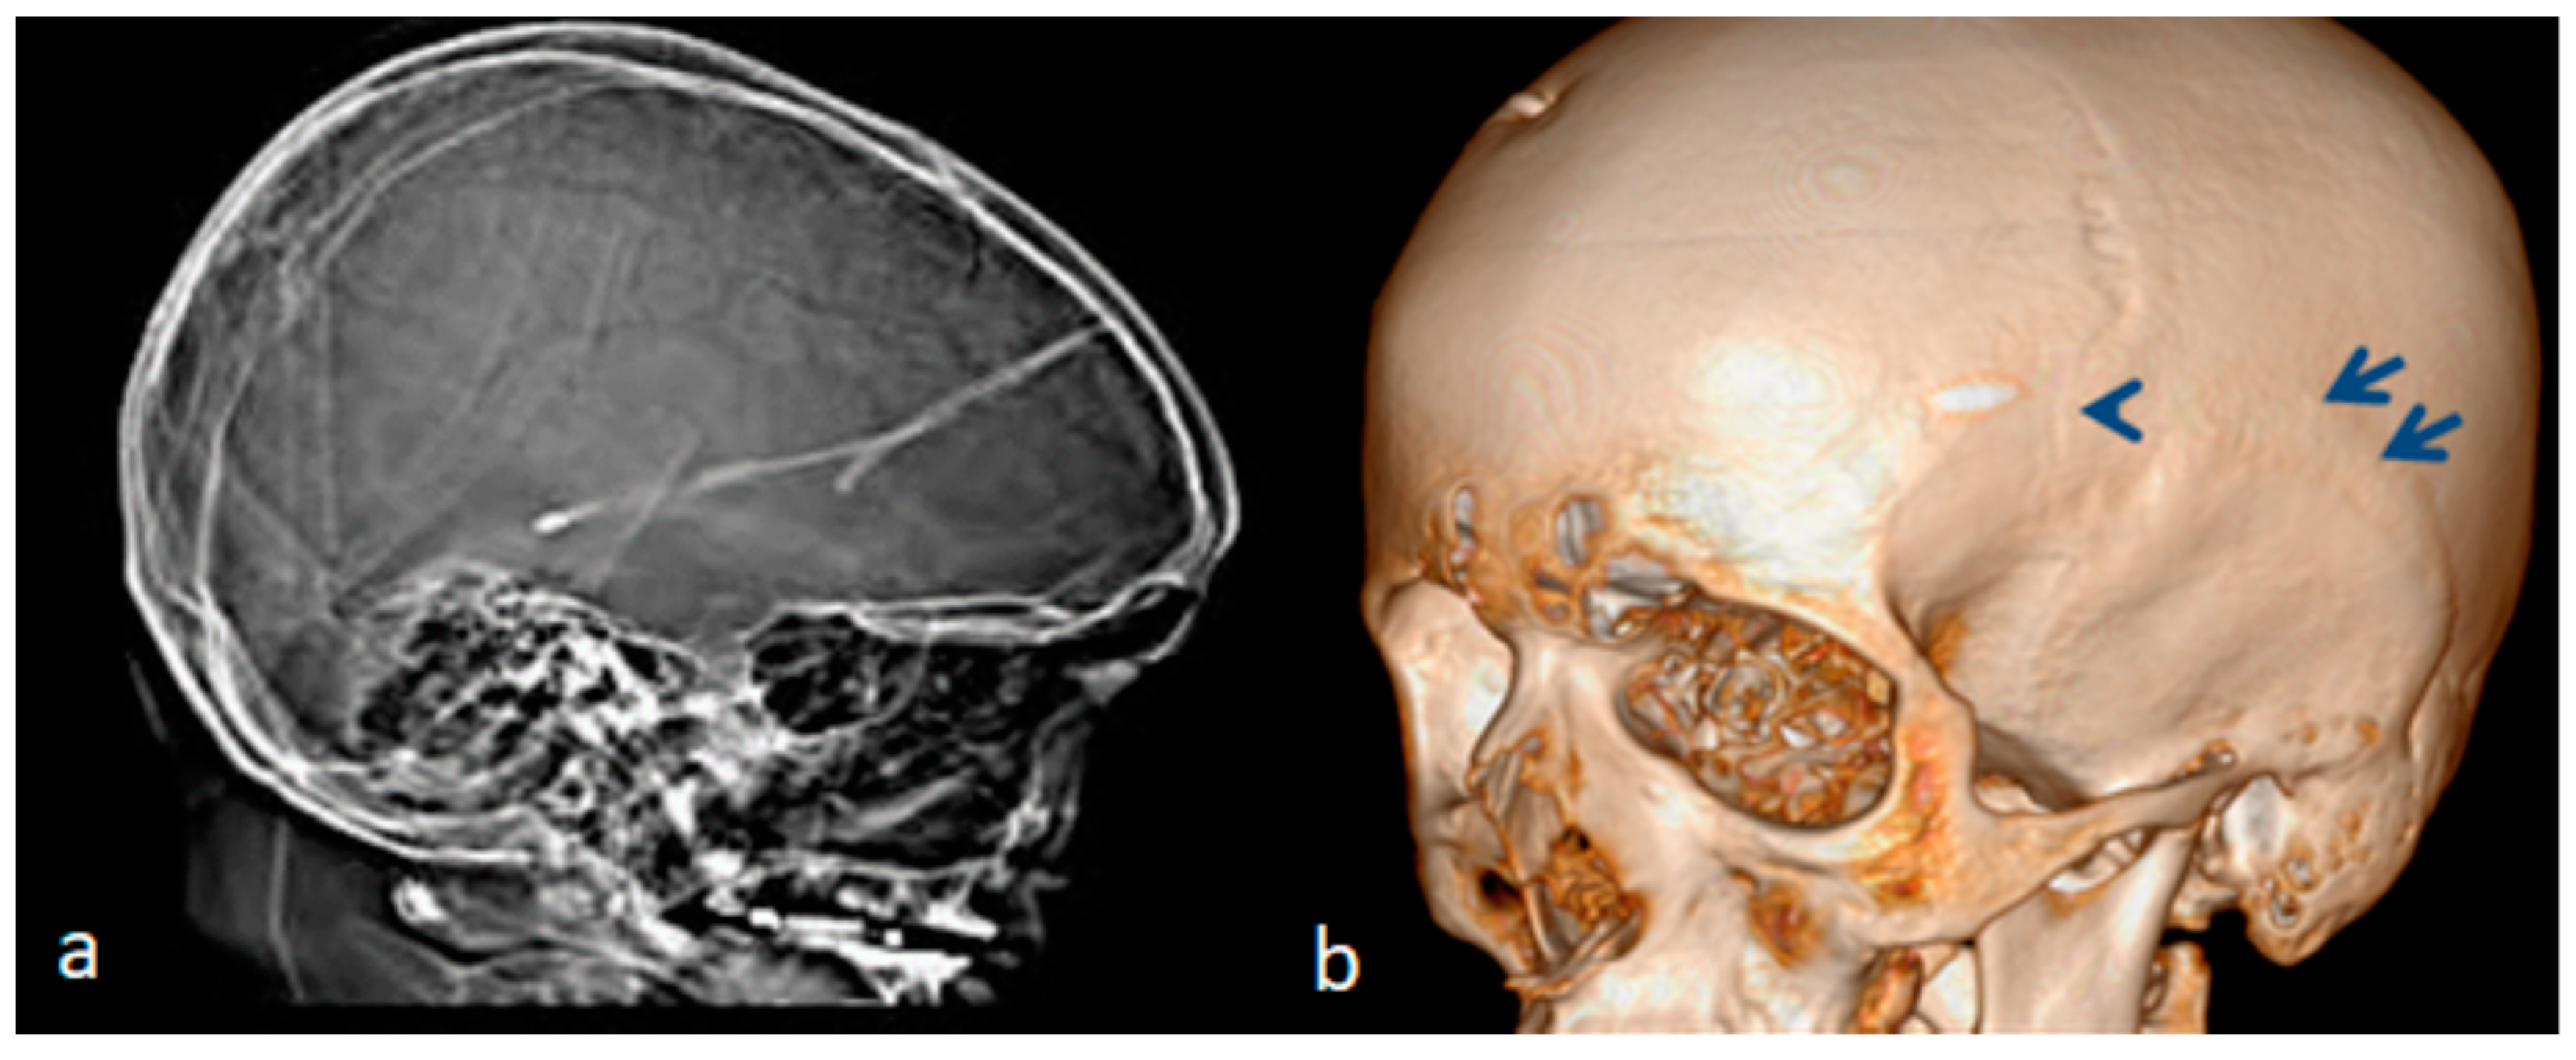

The family history revealed that a younger male sibling was born full-term and was 7 years old at the time of study. In his neonatal period, his pediatrician observed ocular proptosis associated with hypotonia. Ocular proptosis has been confused with exophthalmos. A diagnosis of neonatal thyrotoxicosis was given to the family. The pediatrician based his diagnosis on the maternal history of spontaneous abortions prior to the gestation of the two surviving children. However, neither the mother nor this child showed any clinical or laboratory features suggestive of thyrotoxicosis. The child was extensively investigated to rule out the diagnosis of neonatal thyrotoxicosis. Despite the prenatal investigations during gestation, none of the signs of neonatal thyrotoxicosis were elicited. No fetal or neonatal tachycardia was recorded. His resting fetal heart rate was normal, and no fetal neonatal goiters were recorded. Afterwards, the diagnosis of positional plagiocephaly was issued and the pediatricians suggested the application of “Helmet molding therapy” because of the skull asymmetry. Helmet molding therapy was applied for two years. The incentive for examining this child was as part of our clinical strategy for examining all the family subjects. This child was seen for the first time by the first author at the age of 7 years. He manifested typical marfanoid habitus akin to his older sibling. This can be seen through the clinical documentation, as summarized via his images. Magnetic resonance imaging (MRI) showed the ocular proptosis (arrows) in his neonatal period, which was misdiagnosed as neonatal thyrotoxicosis (Figure 2a). At the age of 7 years, he was referred to our department to check his juvenile scoliosis. He manifested torticollis and cervico-thoracic kyphoscoliosis of 50° kyphoscoliosis. He showed a similar clinical phenotype of marfanoid habitus, craniofacial asymmetry, and dysmorphic craniofacial features, suggestive of Shprintzen Goldberg syndrome (SGS) (Figure 2b). A 3D reconstruction computerized tomography (CT) scan showed craniofacial asymmetry and scaphocephly in connection with the total fusion of the sagittal suture (arrow) (Figure 2c).

Figure 2. (ac). MRI showed the ocular proptosis (arrows) of a newborn which was misdiagnosed as neonatal thyrotoxicosis. The craniofacial asymmetry was totally ignored by the radiologist and the pediatrician (a). The clinical phenotype of the younger sibling at the age of 7 years. He was referred to our department to check his juvenile scoliosis. He manifested torticollis and cervico-thoracic kyphoscoliosis of 50° kyphoscoliosis. He showed a similar clinical phenotype to his older sibling (craniofacial asymmetry and dysmorphic craniofacial features suggestive of Shprintzen–Goldberg syndrome (SGS) (b). A 3D reconstruction CT scan showed craniofacial asymmetry and scaphocephly in connection with the premature fusion of the sagittal suture, and the application of helmet therapy enhanced the cranial asymmetry (arrow) (c).